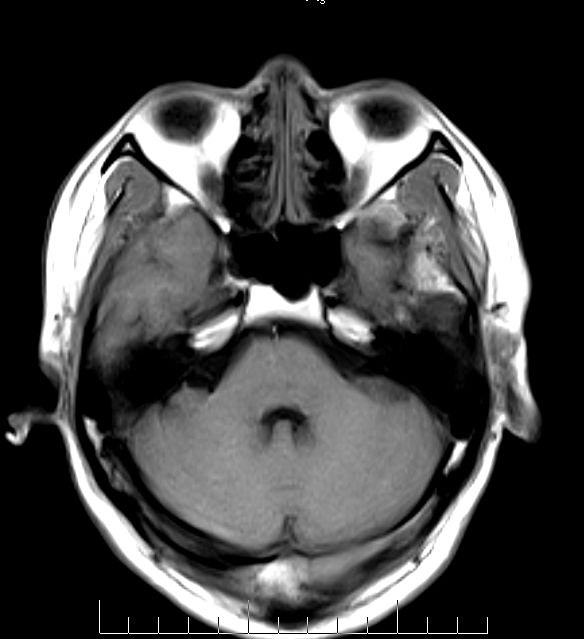

标题: MRI2379:30岁,男,癫痫10年,请各位看一下;CT示:左颞叶钙 [打印本页]

标题: MRI2379:30岁,男,癫痫10年,请各位看一下;CT示:左颞叶钙

左颞叶区见不规则点状混杂信号影

支持2楼 左颞叶区见不规则点状混杂信号影,考虑动静脉畸形。

考虑左侧颞叶脑血管畸形(avm)。----t1低等高混杂信号,t2等高信号周边较多流空血管影[冠状位明显],mra左侧大脑中动脉受压,远侧聚集.